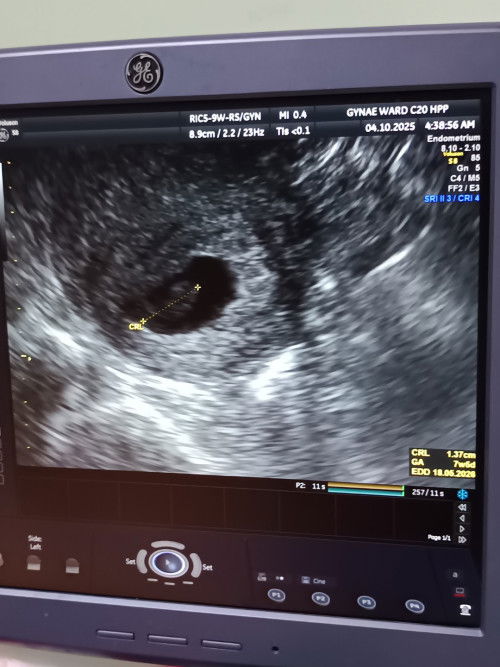

9weeks pregnant.

Doktor cek bby bru 7weeks, no heartbeats, ada spotting. Patut ka double cek di klinik swasta.

untuk double confirm, better g klinik swsta, kalau tgk gambar ni area luar dari kantung dah ada bleeding, tingal nk lekang je, apa2 pun keputusan terima hati terbuka. .